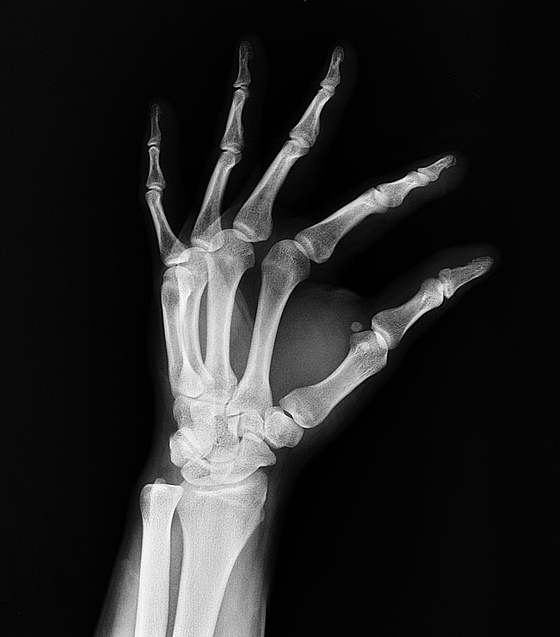

Según su forma, los huesos se clasifican en:

– Largos: huesos con cavidad medular, como el fémur y las costillas.

– Cortos: huesos del carpo y del tarso (mano y pie).

– Planos: huesos de la bóveda craneal, la escápula, el esternón y la pelvis.

– Irregulares: huesos de la base craneal y de las vértebras.

El llamado hueso largo se suele describir como prototipo de hueso porque en él se aprecian claramente todos los segmentos óseos. Esos huesos largos son el húmero, el fémur, la tibia, entre otros, y los segmentos que lo componen son tres:

– Epífisis: constituyen los extremos o terminaciones del hueso.

– Diáfisis: porción principal del hueso, la parte alargada, la cual es semicilíndrica y compuesta de tejido compacto.

– Metáfisis: es la zona de ensanchamiento.

También encontramos la fisis o cartílago de crecimiento, que es una lámina de cartílago que se localiza entre la epífisis y la metáfisis y se le conoce como línea o placa fisiaria o de crecimiento. Cuando el crecimiento se frena, los cartílagos gradualmente se osifican, lo que se llama cierre del cartílago de crecimiento.